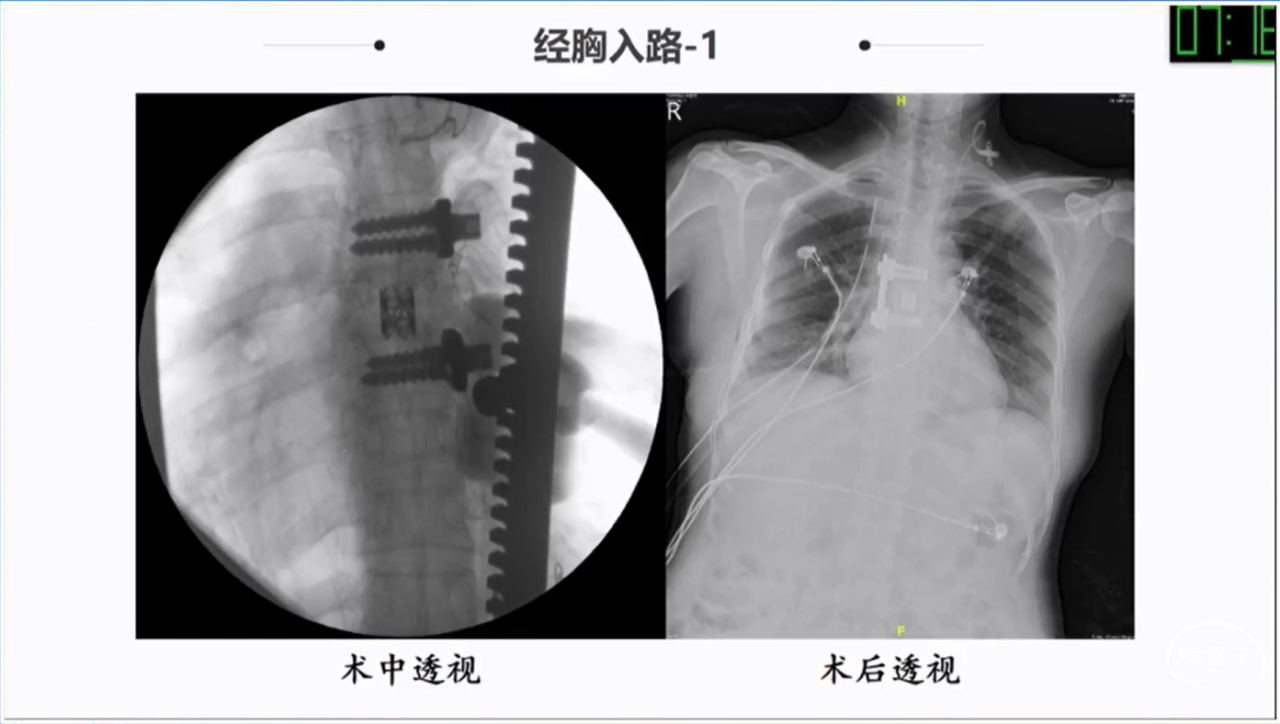

椎旁肿瘤种类多样,手术切除是主要的治疗方法;血供一般,病灶内切除减容,为肿瘤的全部切除提供有利条件;Witlse入路治疗椎旁巨大肿瘤优势明显;椎体破坏、血管侵犯、胸膜下的病例尽量选用经胸入路或者联合入路。

· 椎体破坏、血管侵犯、胸膜下的病例尽量选用经胸入路或者联合入路